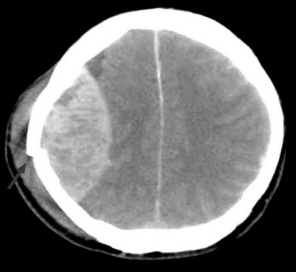

Adolescente, 13 anos, vítima de atropelamento por carro, apresentou perda da consciência, logo após o trauma , mas ao chegar a equipe de resgate, a criança estava alerta, ECG de 14, apresentando intensa cefaleia e discreta hemiparesia à esquerda. Após 2 h na sala de emergência, apresentou rebaixamento do nível de consciência e piora neurológica. Foi submetida à TC de crânio de urgência.

De acordo com a imagem, o diagnóstico dessa criança é: